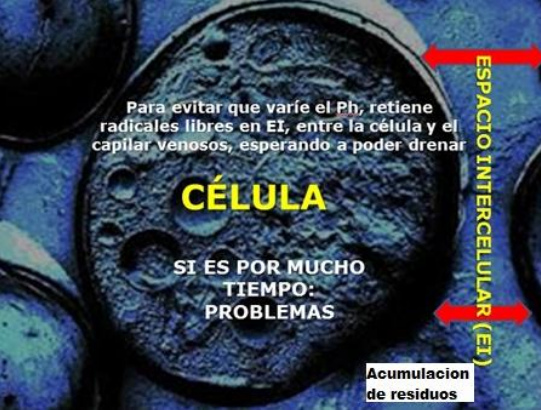

Las células son siempre rodeadas por el espacio

intercelular (EI), llamado también "capilar" [2]

Ese capilar es como una

zona tapón con la cual las células "juegan"

depositando nutrientes y residuos como lo

necesitan. Por eso cuando la persona ha comido

así los capilares están llenos de nutrientes y

después de la noche todos los nutrientes son

consumidos por las células.

[Suplemento: El escenario con los tóxicos y

con la muerte de la célula

Cuando vienen muchos tóxicos en ese espacio

intercelular (EI, capilar)

así todo el espacio intercelular (EI, capilar)

está lleno de basura tóxica enrodeando la

célula. La célula no recibe nutrientes más y

está en peligro de ahogar y de morir porque

con los tóxicos la célula no puede vivir.

La alimentación que provoca ácidos provoca

basura ácida en el espacio intersticial y mata

la célula

La alimentación que provoca ácidos en el organismo

provoca que los ácidos se acumulan en la sangre.

El cuerpo quiere equilibrar la acidez del valor pH

de la sangre. Así el cuerpo retiene los radicales

ácidos libres en el espacio intersticial para

drenarlos más tarde. Puede ser que por el bloqueo

de filtros o por la comida mala siguen más toxinas

ácidas y sigue o se aumenta (incrementa) ese

depósito de ácidos en el espacio intersticial. Con

eso van a ser problemas y al fin va a ser "ahogada

por sus propios residuos".

El proceso de acumulación de residuos tóxicos -

la célula "ahogada"

Acumulando residuos tóxicos siempre significa de retener

ácidos. La basura viene en forma de ácidos. El ácido en el

cuerpo se mide con la unidad "valor pH" en la sangre

[nota1].

El cuerpo siempre

quiere equilibrar ese valor pH en la sangre. Retiene

los radicales ácidos libres en el espacio intersticial

[intercelular, en el capilar] (fig. 2) "entre la

célula y el capilar venoso" como depósito para

drenarlos más tarde. Cuando - por obstrucción de los

filtros o por exceso de toxinas - sigue más

acumulación de residuos así el oxígeno de la sangre no

puede lograr las células más. Además la célula no

puede descargarse de los residuos más y así "la célula

terminará ahogada por sus propios residuos".